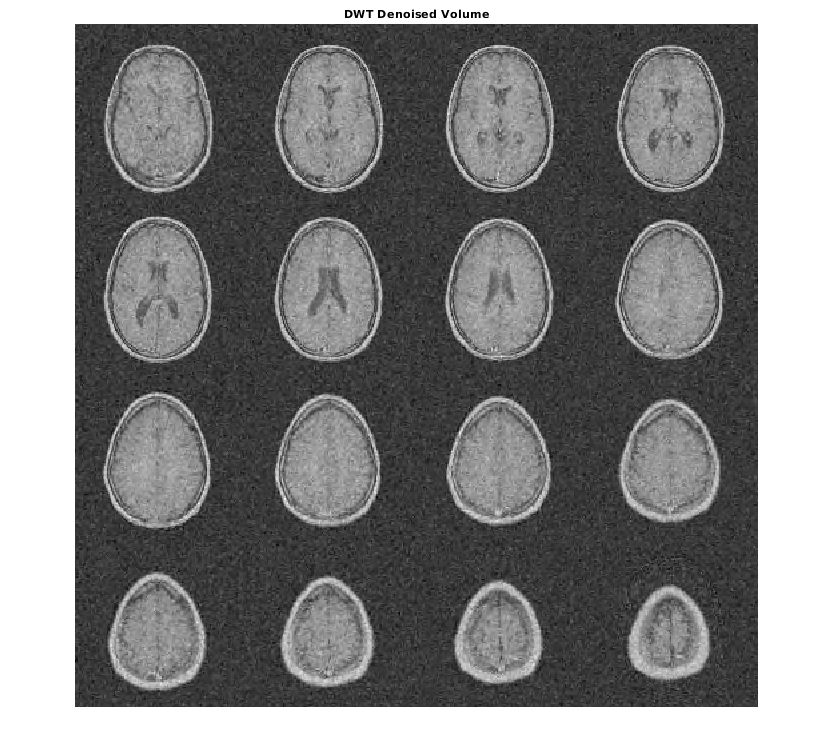

Denoise набор данных MRI вниз к уровню 4 с помощью и DTCWT и DWT. Подобные длины фильтра вейвлета используются в обоих случаях. Постройте получившийся ОСШ как функцию порога. Отобразите denoised результаты и для DTCWT и для DWT, полученного в лучшем ОСШ.

[imrecDTCWT,imrecDWT] = helperCompare3DDenoising(origMRI,noisyMRI);

figure montage(reshape(imrecDWT,[128 128 1 16]),'DisplayRange',[]) title('DWT Denoised Volume')